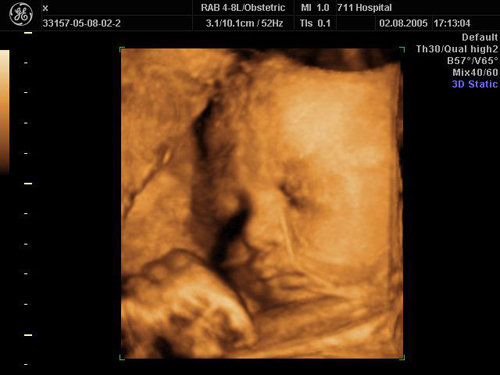

三維(wei)容積探頭檢(jian)查中(zhong)

胎兒三維(wei)超聲圖像(鼻唇部(bu))